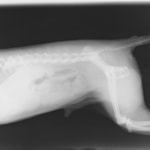

術前レントゲン

腹部臓器が胸腔内に脱出し、腹部と胸部の境界および心臓や肺の陰影が不明瞭になっています。また、胸腔内に消化管のガス陰影が認められます。

術後レントゲン

腹部臓器が腹腔内に戻り、腹部と胸部の境界および心臓や肺の陰影が明瞭に見えるようになりました。